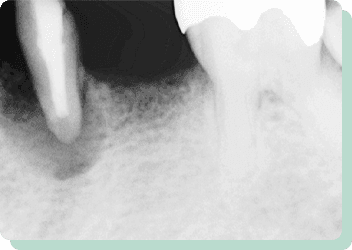

向かって左の歯は、根を支える骨の状態が悪く、残せるかどうか分からない位の歯でした。入れ歯やブリッジでの対応は難しく、右側にインプラントを入れてしっかりと咬合させることにより左の歯への負担を減らすことができました。結果10年以上経過した現在も問題なく機能しています。

リスク:疼痛・咬合時痛・冷水痛・出血・インプラント手術による歯ぐきなどの損傷・インプラント周囲炎など

費用:インプラント治療1本あたり440,000円